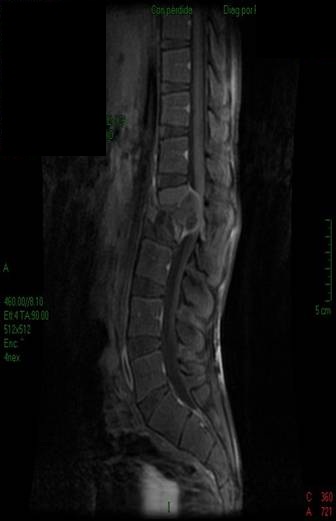

- Figura No 2a

- Figura No 2b

- Figura No 2c

- Figura No 2d

- Figura 2 Texto